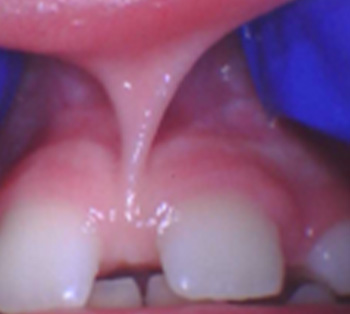

Frenectomy: Before and After

• Lip Tie

A restrictive upper lip frenum may prevent the lip from flanging outward during feeding, contributing to poor latch, air intake, or difficulty maintaining suction.